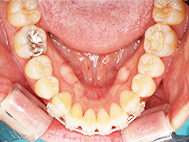

Before

左上の前歯内側に入っている下の前歯ガチャ歯

左上前歯が下の歯の内側に入っているのが気になるとの事で来院されました。目立たない矯正治療を希望しているとのこでした。 上顎の装置は、歯の裏側(リンガル装置)で下顎は表側で矯正治療を行いました。口を閉じた時、上の前歯が内側に入っている為に下の歯を前に押し出している状態でした。その為、上の歯を前に出すだけではその歯が下とのかみ合わせの関係で、前に飛び出すような治療となってしまいます。 今回の症例ではシュミレーションを見て頂き、下の歯も治療し、内側へ下げることによって上の歯も飛びだすことなく、キレイにおさまることを説明し、上下一緒に矯正することをお勧めさせて頂きました。